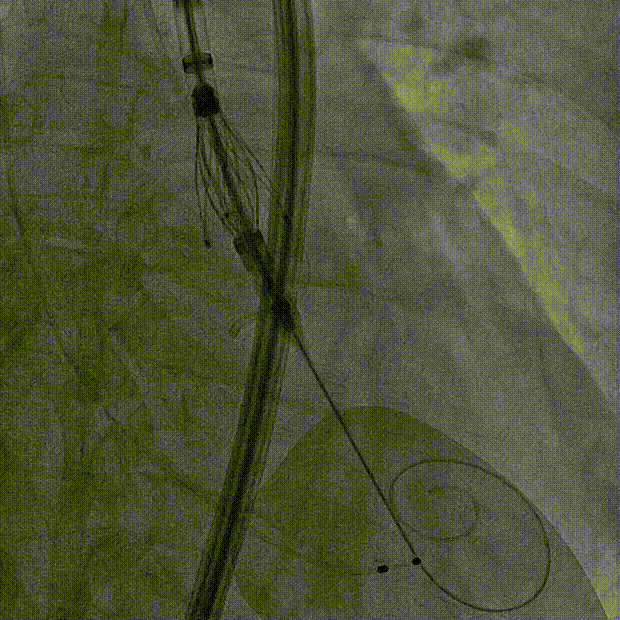

长鞘植入

输送器定位

右窦中心对齐

定位键窦对齐

无窦确认

右窦观察

左窦确认

深度确认

一键脱钩

术后造影